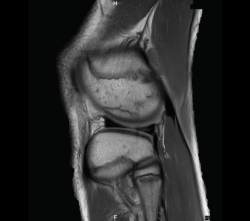

4.3. Osteocondritis

En la osteocondritis se aprecia una lesión subcondral caracterizada por resorción ósea, colapso y la formación de un secuestro.

El estudio por RM es una herramienta valiosa para diagnosticar e identificar las lesiones del cartílago. Conocer el aspecto del cartílago y saber cuánto y cuándo se lesiona, basándose en las clasificaciones actuales, permiten al radiólogo proporcionar la máxima información al clínico(20).

Figura 53. Corte de secuencia sagital (A) y axial (B) T2 Fat-Sat de RM de rodilla: lesiones osteocondrales en el fémur y la rótula.

Numerosos estudios demuestran la utilidad de la RM para definir la estabilidad o inestabilidad de la lesión en la osteocondritis, destacando su carácter no invasivo y la capacidad de valorar la progresión y la respuesta al tratamiento(21)(Figuras 53 y 54).